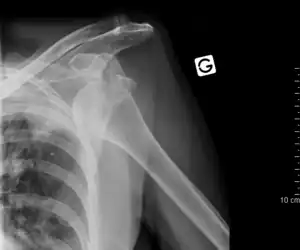

Luxation de l'épaule ou scapulo-humérale

La luxation scapulo-humérale ou gléno-humérale, le plus souvent antérieure « pure » mais peut s'accompagner d'une fracture de la grande tubérosité (ou trochiter) dans ce cas la réduction est la même, mais il faudra fixer le fragment au reste de l'humérus. Quand il n'y a pas d'arrachement osseux, la réduction doit être rapidement réalisée, pas tant pour l'avenir de l'articulation mais plutôt pour la moindre difficulté de réalisation. En effet de nombreuses techniques ont été décrites, la plus connue est celle d'Hippocrate, consistant à tirer sur le bras dans l'axe en plaçant le pied de l'opérateur dans l'aisselle du patient. Cette technique se heurte à de nombreux échecs car source de douleurs importantes, or la réussite d'une réduction dépend directement du relâchement musculaire du patient. Ceci explique la variabilité individuelle, certaines luxations de l'épaule se résolvant sans aucune anesthésie, ni sédation, simplement avec une analgésie légère, et d'autre se terminant au bloc opératoire sous anesthésie générale après plusieurs tentatives infructueuses (en particulier chez un sujet jeune et musclé pour lequel le relâchement musculaire n'a pas pu être obtenu). De toutes façons la réduction est un geste médico-chirurgical, les risques sont la blessure du nerf circonflexe qui détermine la sensibilité du galbe de l'épaule, il peut être abimé au moment du traumatisme comme lors du traitement et sa blessure doit être recherchée et consignée sur le dossier médical. Les autres blessures sont plus rares, signalons juste le risque de fracture de la tête humérale sur le bord de l'omoplate chez un patient âgé à os fragile. Tout ceci est valable pour la luxation en avant de l'omoplate mais il existe des luxations postérieures, donc en arrière de diagnostic plus difficile (pouvant être une lésion traumatique suivant une crise d'épilepsie), et des luxations inférieures "erecta", le bras restant levé vers le ciel sans possibilité d'abaissement. Le déplacement étant particulier, la réduction nécessite toujours une anesthésie générale. Les luxations répétées ou itératives ne guériront plus et nécessiteront une stabilisation chirurgicale pour éviter les récidives.